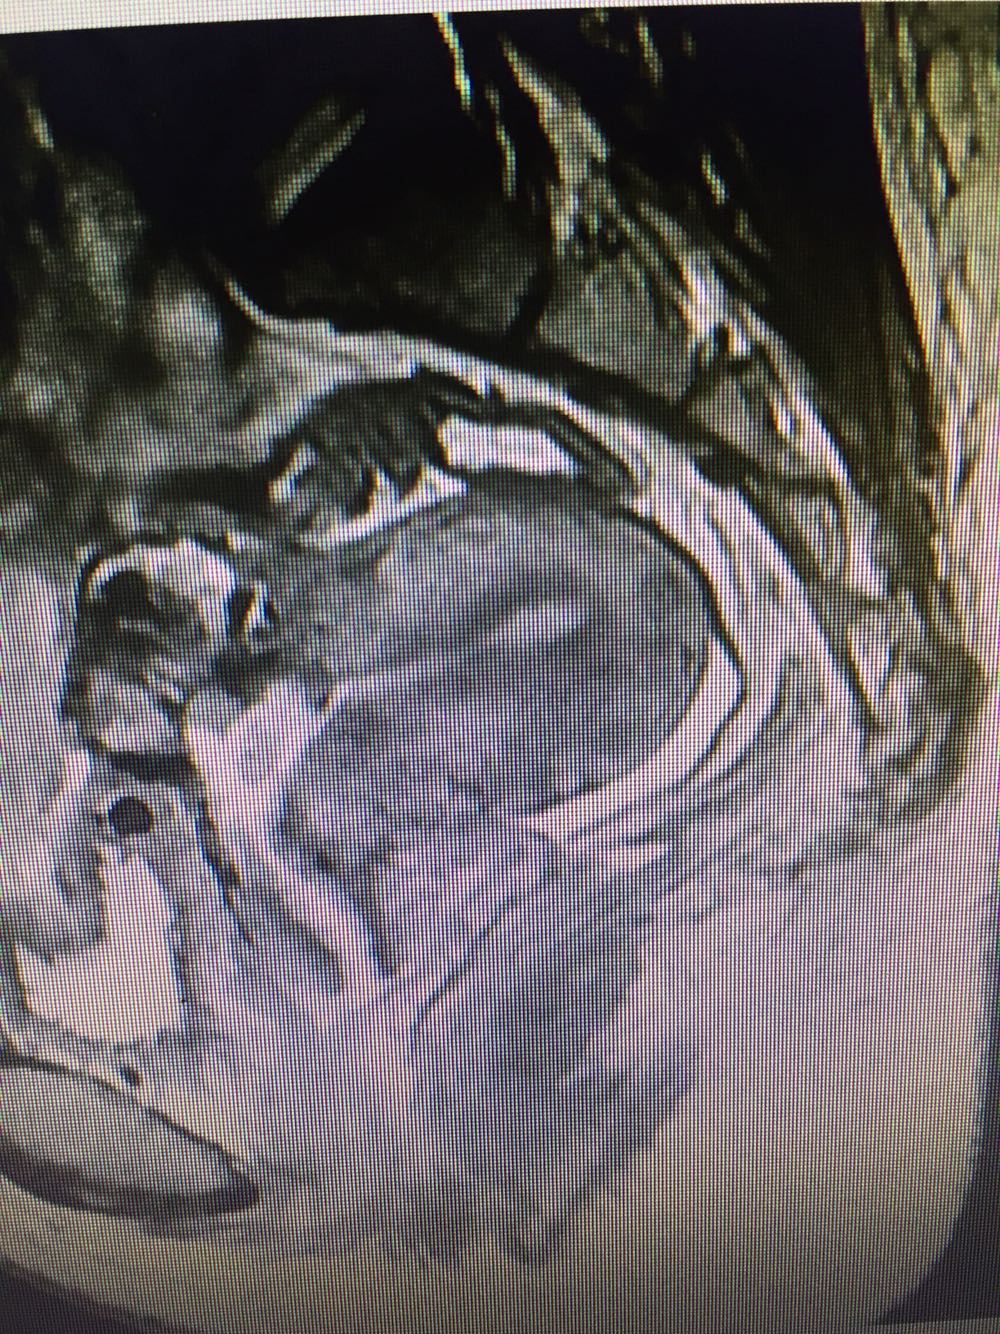

子宫动静脉瘘

诊断:阴道出血原因待查:子宫动静脉瘘? 治疗:宫腔镜下病灶定位+腹腔镜下子宫病损切除术+盆腔粘连松解术。

随访:病理结果回报:送检组织镜下见平滑肌组织中有数个粗大、扩张迂曲的血管,其内可见血栓,另可见数个粗细不等的中等大小血管,结合临床,符合动静脉瘘的改变。